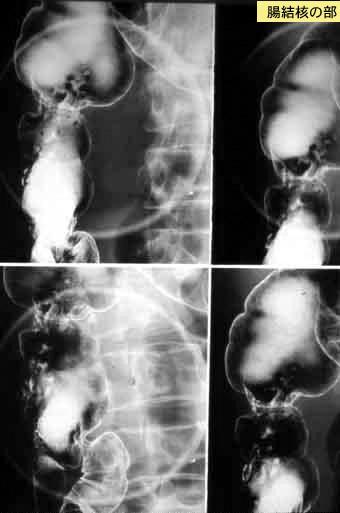

Tuberculosis del Colon que se extirpó por presentar tuberculosis activa en Colon Ascendente y Ciego, y Cáncer Avanzado de Colon Transverso

Tokyo Pref., Centro Nacional de curaciones de Cáncer, Hospital Central y Centro Kyusyu de Curaciones de Cáncerc

Enfermedad Inflamatoria - Ulcerativa/Tuberculosis

colon/ascendente

Rayos X